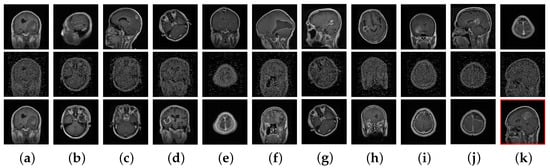

Finally, for visual analysis, Figure 5 shows an example query image and its corresponding retrieval results for both the non-secure and proposed secure retrieval techniques (where ). Though, most of the images retrieved using a cipher image query were different from those retrieved using plain image retrieval, inter-class discrimination was still preserved in the encrypted domain, as shown by the correct retrieval results.

Figure 5.

Examples of non-secure and secure retrieval of images similar to a query image from the database. (a) Query images and (b–k) retrieved images. The non-secure retrieval results are in the first row, and the secure retrieval results are in the second row, with their decrypted images in the third row. The images were encrypted using the proposed encryption method with different keys. Incorrect retrieval results are in red boxes.